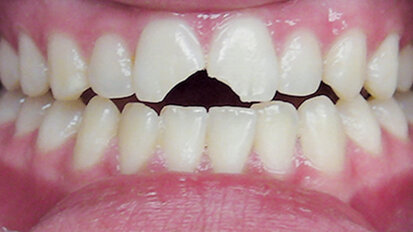

Hybridní terapie alignery